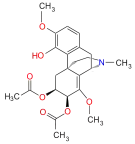

Oripavine derivatives

Thienorphine

- 7-PET

- Acetorphine

- Alletorphine (N-allyl-noretorphine)

- BU-48

- Buprenorphine

- Buprenorphine-3-glucuronide

- Cyprenorphine

- Dihydroetorphine

- Etorphine

- Homprenorphine

- 18,19-Dehydrobuprenorphine (HS-599)

- N-cyclopropylmethylnoretorphine

- Nepenthone

- Norbuprenorphine

- Norbuprenorphine-3-glucuronide

- Thevinone

- Thienorphine

Structures

| Oripavine derivatives | ||||

|---|---|---|---|---|

7-PET 7-PET |

Acetorphine Acetorphine |

Alletorphine Alletorphine |

BU-48 BU-48 |

Buprenorphine Buprenorphine |

Cyprenorphine Cyprenorphine |

Dihydroetorphine Dihydroetorphine |

Etorphine Etorphine |

Homprenorphine Homprenorphine |

18,19-Dehydrobuprenorphine 18,19-Dehydrobuprenorphine |

N-cyclopropylmethylnoretorphine N-cyclopropylmethylnoretorphine |

Nepenthone Nepenthone |

Norbuprenorphine Norbuprenorphine |

Thevinone Thevinone |

Thienorphine Thienorphine |